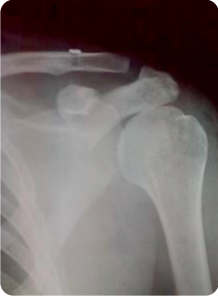

Radiografía de hombro en donde se aprecia el implante colocado y la lesión perfectamente reducida